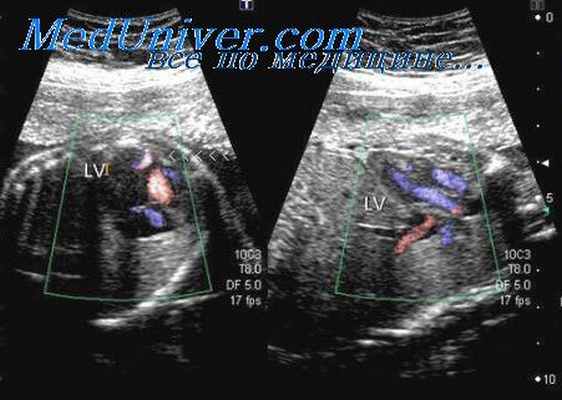

Транспозиция аорты и легочного ствола достаточно просто диагностируется с помощью обычной эхографии, если при осмотре сердца плода выполняется прицельное определение их расположения. Так как ход этих сосудов в большинстве случаев хорошо визуализируется при цветовом картировании, это прекрасно помогает устанавливать диагноз даже в тех случаях, когда качество серошкального изображения ограничено за счет эффекта «акустической тени», возникающего от ребер.

Двойное отхождение аорты и легочного ствола от правого желудочка, их транспозиция, коарктация аорты, стеноз артериального протока и тетрада Фалло идентифицируются с помощью цветовой допплерографии как непосредственно путем визуализации главных сосудов, так и опосредованно путем обнаружения сочетанных аномалий сердца.